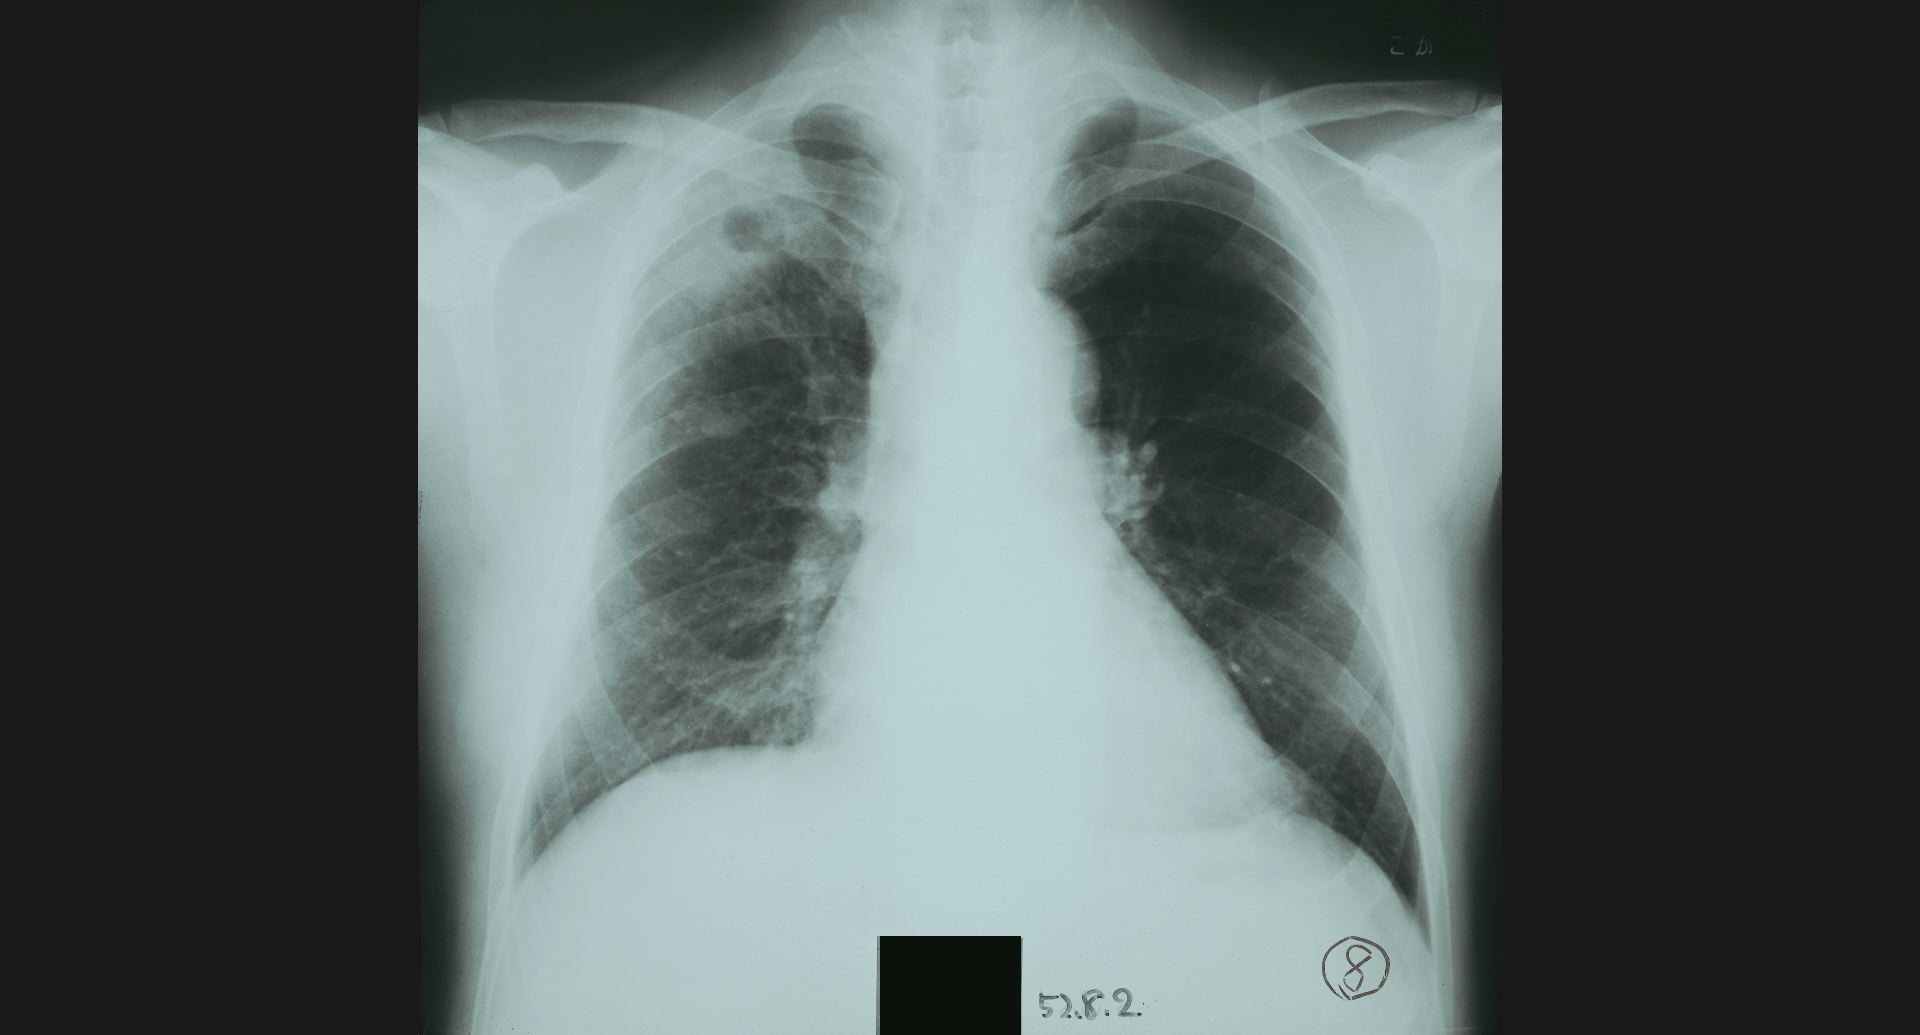

fig.9(94KB) :Pneumoconiosis

細かい斑状陰影。